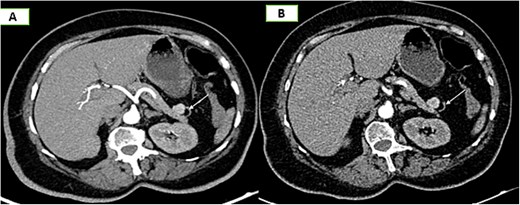

On the complementary CT scan, this lesion exhibits the same tissue characteristics and enhancement as the spleen (Fig. 2), along with its own vascularization through a distinct vascular pedicle (Fig. 3), which is more suggestive ‘of an accessory spleen than an insulinoma of the tail of the pancreas.’

Axial sections of an abdominal non-contrast CT scan (A) and in the arterial phase (B) reveal a nodule adjacent to the tail of the pancreas that is hypervascular on arterial phase and follows the same pattern of enhancement as the spleen.